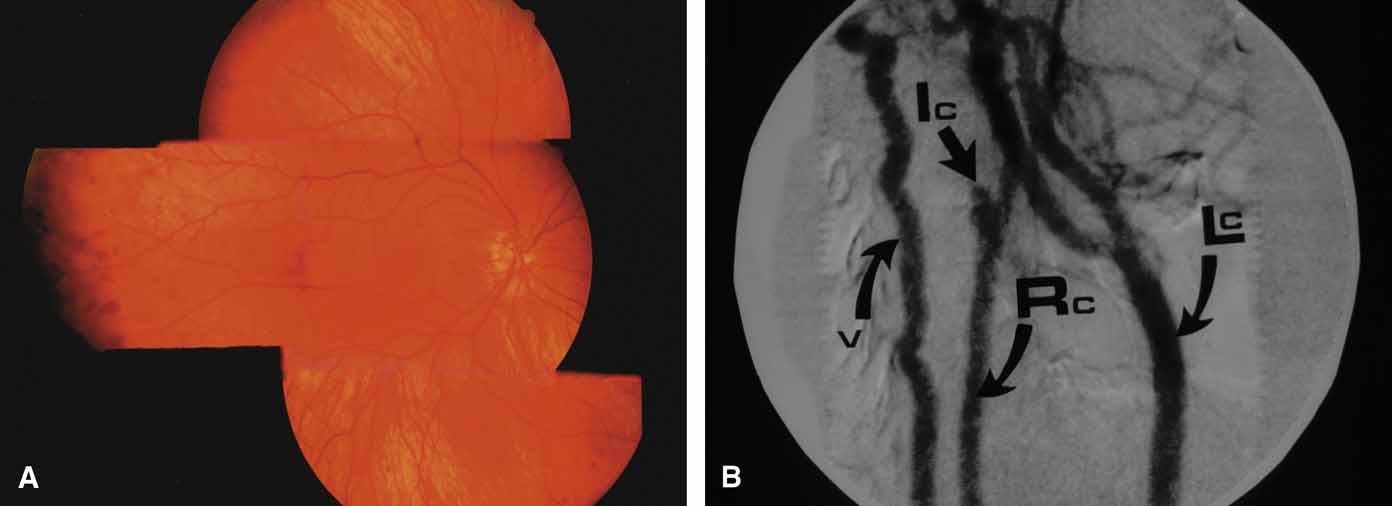

Central Retinal Vein Occlusion (CRVO)

The vascular thrombosis in central retinal vein occlusion is believed to lie within the optic nervehead at the level of the lamina cribrosa or behind where the vein and the artery share a common adventitial sheath.127 Rarely, an initial period of hypotony may develop after an acute central retinal vein occlusion.128 If major retinal capillary compromise is present,129 iris neovascularization may develop within 1 to 3 months and produce peripheral angle synechiae and angle closure. Ischemic central retinal vein occlusions represent less than one-third of all central venous obstructions and are characterized by multiple cotton-wool spots and a poor visual acuity, typically less than 20/200 (6/60) (Fig. 21).

Fig. 21 Ischemic central retinal vein obstruction. A. Heavy intraretinal hemorrhages, cotton-wool spots, and vision of 20/400 (6/120). B. Fluorescein angiogram clearly demonstrates severe loss of capillary bed perfusion.

Although cotton-wool spots represent infarcts of the nerve fiber layer and may be a clinical sign of ischemia, any eye with a central retinal vein occlusion should be monitored with monthly slit lamp and gonioscopic exams. The onset of neovascularization of iris or angle warrants pan retinal photocoagulation to try to prevent neovascular glaucoma.130,131 Between 10% and 20% of eyes with central retinal vein occlusion may convert from an initial nonischemic angiographic picture to ischemia, especially if the initial vision is poor. The greatest risk of conversion to ischemia is found 1 to 3 months following the occlusion but can occur even later. Nonischemic occlusions (Fig. 23) should be followed closely during this time period.

Fig. 23 Nonischemic central retinal vein obstruction. A. Dilated, tortuous veins, minimal intraretinal hemorrhages, and 20/40 (6/12) vision. B. Fluorescein angiogram showing minimal damage to capillary bed. Despite the lack of ischemic capillary damage on the present study, up to 20% of patients may convert to the ischemic type, necessitating careful follow-up examinations.

Although most practices now follow the clinical exam to evaluate of CRVOs instead of fluorescein angiography, significant nonperfusion on angiography still guides some clinicians toward prophylactic pan retinal photocoagulation. In the past, some utilized the electroretinogram (ERG) to define those eyes at greatest risk for neovascularization.132 The ERG was of particular value in those eyes, which confounded conventional angiographic evaluation due to a small pupil, cataract, or those that might have undetectable peripheral ischemia.